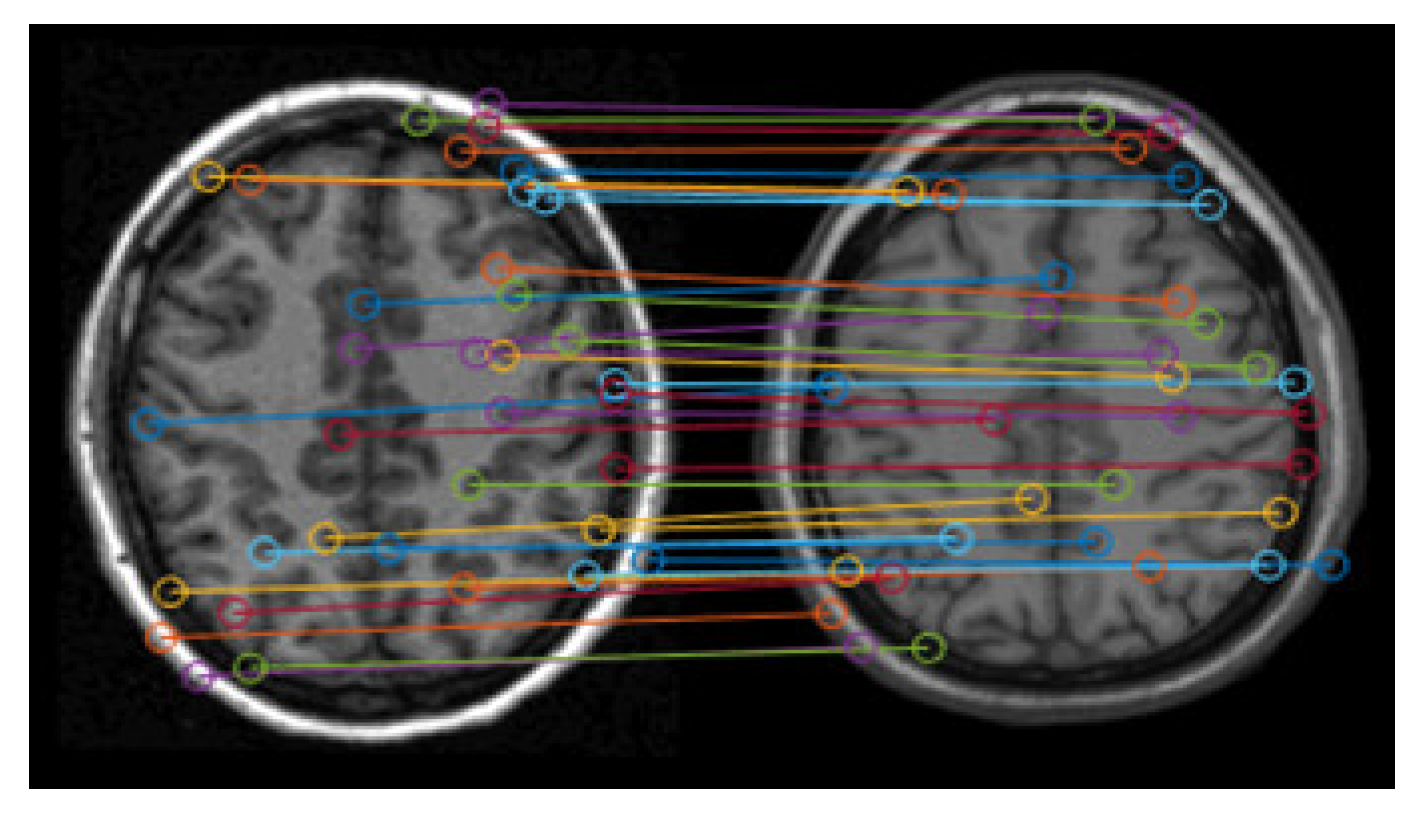

Figure 4 shows the matching results of the feature points. It can be seen that there are lots of error matching pairs of feature points, which may lead to the distortion of registration.

Figure 4. Matching results of feature points.